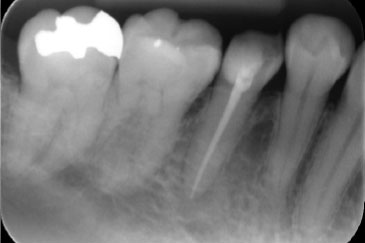

現在の治療費と異なる場合がございます。最新の治療費は料金表をご確認ください。CASE 1

BEFORE

AFTER

基本情報

| 年齢・ 性別 |

40歳・女性 |

|---|---|

| 主訴 | 虫歯・右下5 |

| 治療 内容 |

左下5・根管治療 |

| 治療 期間 |

2回 |

| 治療費 | 保険診療 約3,000円 |

| リスク・ 副作用 |

神経を取ってもすぐに痛みが引かない可能性があります。 神経の治療の刺激により、数日痛み・腫れがでる可能性があります。 細く繊細な器具を使用するため、器具が破折する可能性があります。 複雑な神経の治療では、大学病院もしくは専門医による治療が必要となることがあります。 または抜歯になることもあります。 |